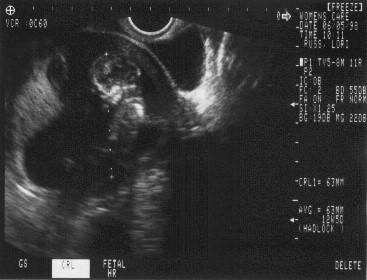

• Click here for full size picture!5th June 1998 - Our first doctor's appointment (damn HMO's). Doc says, "Sure enough there's a critter in there, and by the way here is a nice black and white picture to take with you." That was nifty!

• 23rd July 1998 - Second and final ultrasound today (if nothing goes wrong).  We got to see a healthy developing baby girl.  Brain, heart, skeletal and organ development is on track and looking good.  We decide on the name for sweet pea - Caitlin Elizabeth Russ.  Take a look at the sonograms we have from the ultrasound.

Click here for full size picture!